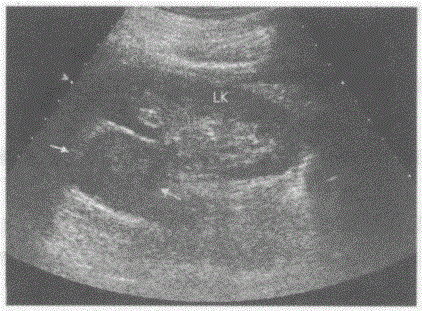

问题 临床资料:女,44岁,自述近期间断发作性心悸、气短,严重时恶心、呕吐,视物模糊,血压190/100mmHg,持续时间数十分钟至数小时不等。 超声综合描述:左肾上极可见3.4cm×4.0cm圆形低回声区(箭头所示),边界清晰,有完整的强回声包膜,受其推挤左肾上极形态失常,CDFI:低回声区内可见深入支动静脉血流信号。见下图及彩图。 {图1} 超声提示:

选项 A.左肾上腺嗜铬细胞瘤 B.平滑肌肉瘤 C.左肾癌 D.左肾静脉血栓

答案 A